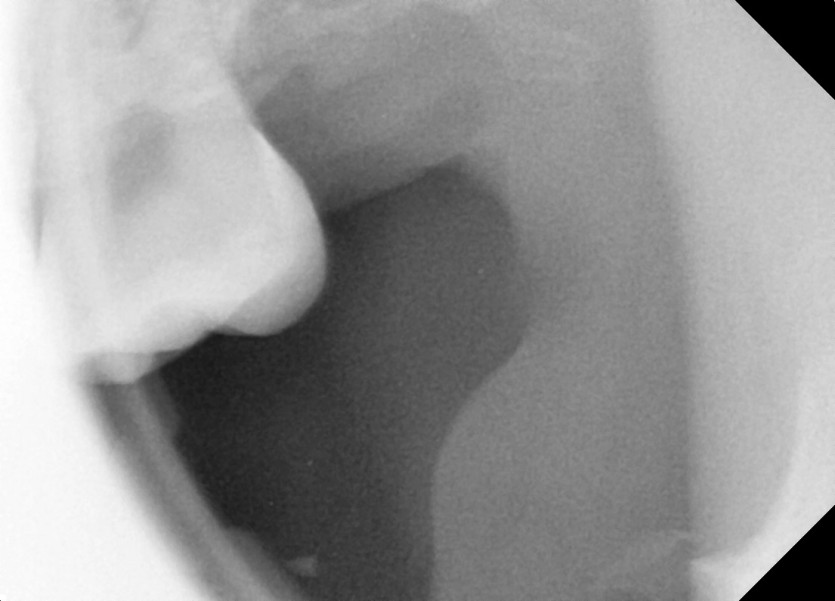

#28,38,48 사랑니 발치

구강 외과 전문의가 당일 발치했습니다.